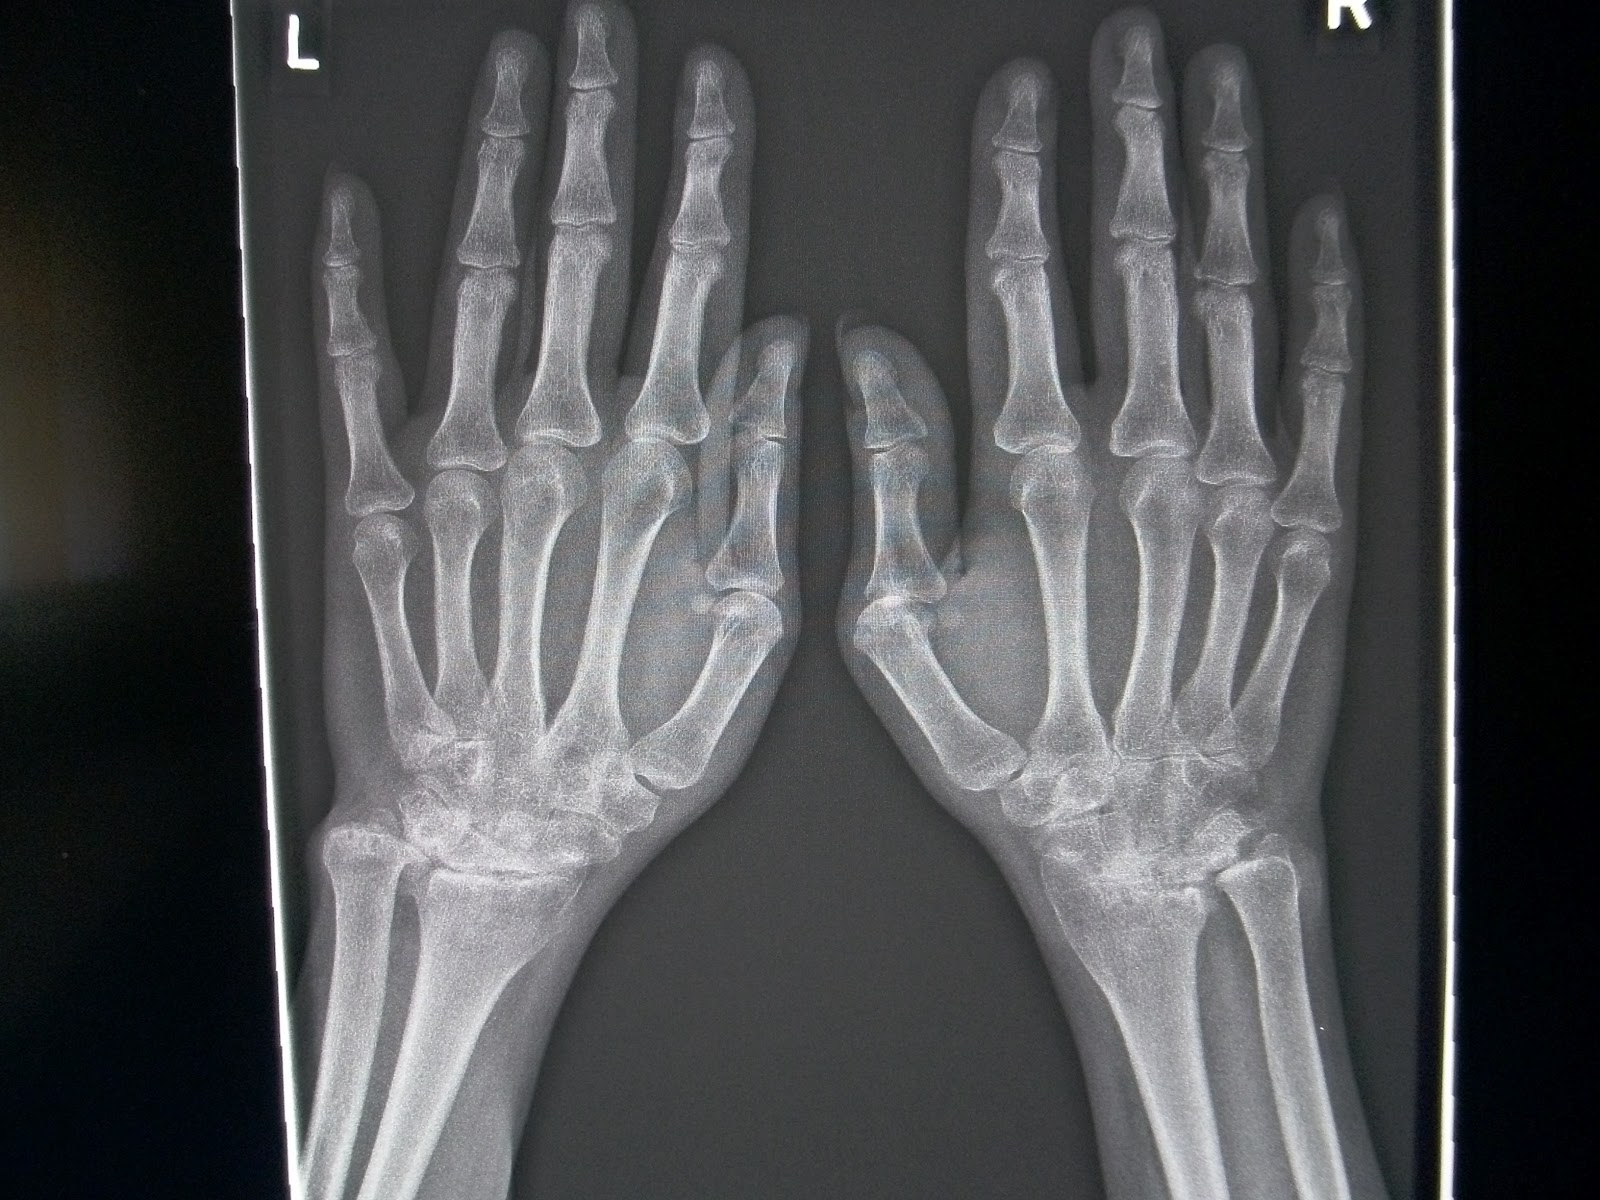

Rheumatologe Rheumatoid Arthritis Radiographic Progression Nodular Rheumatoid Arthritis Icd 10 Rheumatoid nodules are firm, noticeable lumps that form underneath the skin of some rheumatoid arthritis patients. M06.30 is a billable diagnosis code used to specify a medical diagnosis of rheumatoid nodule, unspecified site. It is found in the 2025 version. The code is valid during the. Icd 10 code for rheumatoid arthritis, unspecified. The code is valid during the. M06.39. Nodular Rheumatoid Arthritis Icd 10.